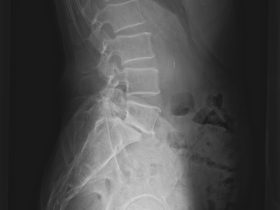

腰椎すべり症を伴う脊柱管狭窄症の原因と症状及び治療方法

「腰椎すべり症を伴う脊柱管狭窄症の原因と症状及び治療方法」 私たちの体は、年をとるにつれ、時間とともに変性することがあります。 その中の一部では、遺伝的要素のために特定の変性状態になることもあります。 …